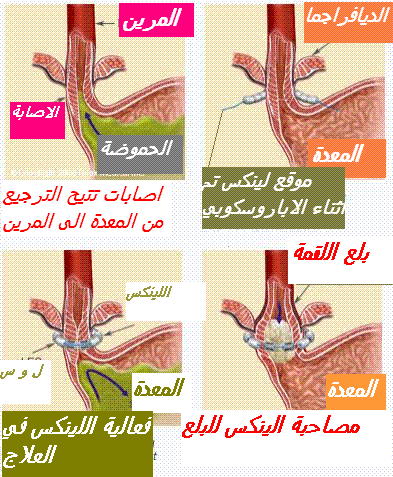

تحتل أدوية م م ب المحل الرئيسي في أخذ موقف علاج حالة الارتجاع المعدي المريئي. يبات ا م م أقل حموضة وبالتالي أقل تسمما للغشاء المخاطي المريني (13) الأمر الذي يؤول الى سرعة التئام الآفات أو جروح الالتهابات المريئية (14). بجانب تحقيق وتراجع الأعراض الناجمة عن الارتجاع المعدي المريئي يتم اللجوء الى تناول م م ب . بجانب تحقيق وتراجع اعراض الناجمة عن الارتجاعي المعدي المريئي. يتم اللجوء لتناول م م ب قصد التئام التهاب المريء الناجم عن حالة الترجيع المعدي المريئي للوقاية ضد الانتكاسات التي تبرز بعد التئام الجراح بجانب علاج حالة الجزر المعدي المريئي الذي تخلفه عقاقير ا م م البروتون التميز بالأعراض السريرية و وجود الدم في البراز. تختلف الجرعات الموصي بها حسب وجود أو عدم التهاب المريء. يلخص جدول رقم 1

. تتمثل الأعراض كأول خطوة السريرية في الحرقان، الارتجاع، السائل الحمضي في الفم) .و بدون الإصابة بالتهاب المريء . ما يتم اقتراح قواعد التغذية والنظافة (19) كأول خطوة بالنسبة للأشكال الأقل شدة. وفي حالة الإخفاق أو الأعراض الأكثر شدة يتم اقتراح أدوية م م ب مثل ما توصف مضادات الحمض الألجينية (20) يستخدم حمض الألجنيك، بشكل خاص في طب الأسنان وصناعة الغراء (21) ، أو مضادات ه2 (22) في حالة غياب انجاز الفحوص الإضافية حينما لا يعاني المصاب من علامة التخدير (23)(العمر أقل من 50 سنة و عدم نقص وزن الجسم بجانب عدم تدهور الحالة الصحية و عدم بروز علاقة النزيف الهضمي و عدم الإصابة بسوء البلع و عدم الإصابة بسوء البلع (24) .

في حالة الإصابة بحالة ا م م المصحوبة بالأعراض السريرية بجانب العلامات النموذجية و علامة الحذر (السن الذي يفوق 50 سنة أو فقدان وزن الجسم أو علامة النزيف أو عسر الهضم) . وبالتالي فالتنظير الباطني الطبيعي تحت غلاف العلاج بأدوية م م ب لا تستثني الإصابة بالتهاب المريء يعد سبب بروز الأعراض السريرية ولذلك يتحتم بقدر المستطاع اللجوء الى انجاز التنظير الباطني في غياب تناول م م ب كلما برز شك في الإصابة بحالة ا م م